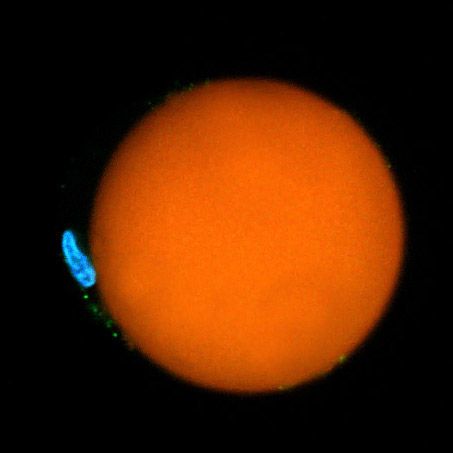

Yun's team did this in two different ways. A soft version was made by injecting a small drop of oil or natural fat lipids mingled with a fluorescent dye into a cell. A hard version used fluorescent polystyrene beads instead. In each case, the entire cell was excited by a nanosecond pulse that produced light, which then became trapped inside the sphere.

The extreme precision of that output is one thing that makes the tiny lasers so promising. The soft droplet versions shift shape ever so lightly when under stress, and that deformation makes a visible change in the laser's emission spectrum, so that even minute changes in the cell can be recorded in fine detail. Similarly the team can produce lasers of slightly different wavelengths by changing the size of the hard beads—enabling them to uniquely color code an individual cell and potentially label thousands of different cells within a single tissue, according to the research published this week in Nature Photonics.